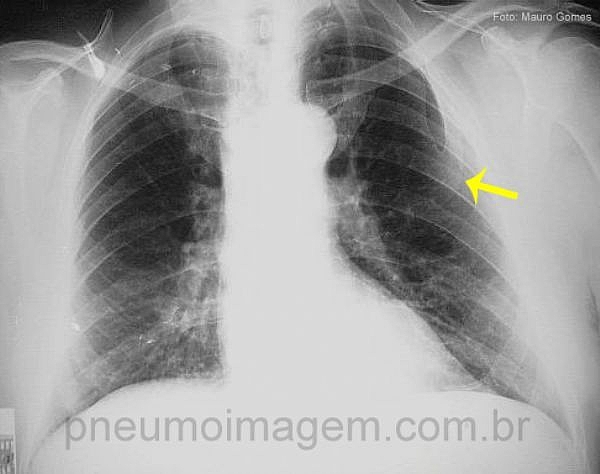

CASO CLÍNICO #32O que a seta aponta nessa radiografia? Deixe os seus comentários abaixo.

What the arrow points in this radiograph? Give your comments below.